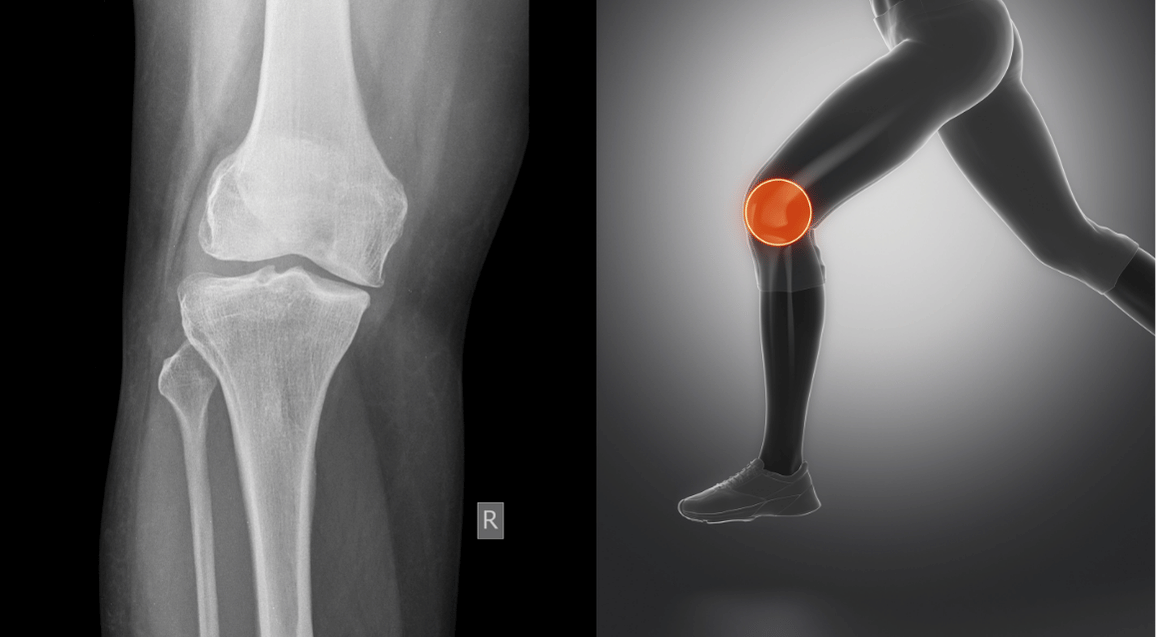

Sports Injuries We Treat in Indore

Click on any injury type to learn more about symptoms, treatment approach, and expected recovery time.

ACL Injury Rehabilitation

Complete ACL rehab program for both surgical and non surgical treatment in Indore.

Meniscus Injury Rehab

Expert treatment for meniscus tears with or without surgery in Indore.

ACL Injury Rehabilitation in Indore

The ACL (anterior cruciate ligament) is one of the most commonly injured ligaments in sports. If you have heard that dreaded “pop” during a sudden twist or landing, you know how serious an ACL tear can be. In Indore, we see ACL injuries frequently in cricket, football, kabaddi, and badminton players.

Meniscus Injury Rehabilitation in Indore

The meniscus is a C shaped cartilage in your knee that acts as a shock absorber. Meniscus tears are common in sports that involve twisting movements. You might feel a pop, followed by swelling and pain when squatting or twisting.